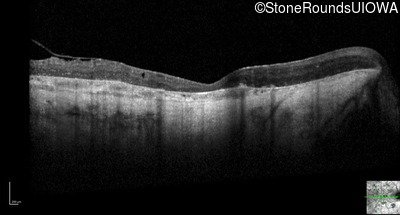

Optical Coherence Tomography - Right - Light Perception

Exemplar / OCT Stack